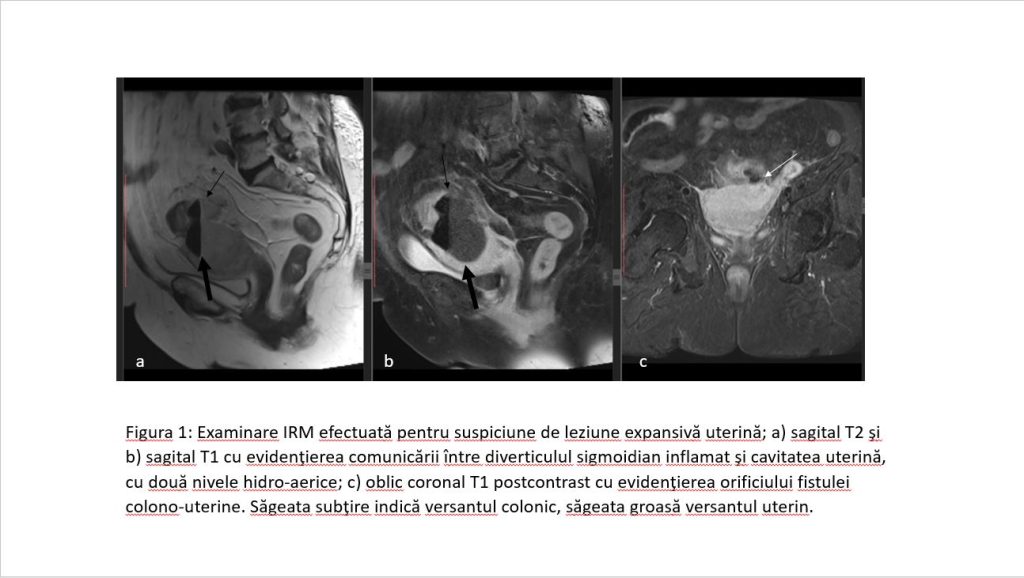

Figura 1: Examinare IRM efectuată pentru suspiciune de leziune expansivă uterină; a) sagital T2 şi b) sagital T1 cu evidenţierea comunicării între diverticulul sigmoidian inflamat şi cavitatea uterină, cu două nivele hidro-aerice; c) oblic coronal T1 postcontrast cu evidenţierea orificiului fistulei colono-uterine. Săgeata subţire indică versantul colonic, săgeata groasă versantul uterin.

Discuție caz 3: diverticulita acută reprezintă inflamația unui diverticul intestinal iar imagistic se pune în evidență îngroșare parietală a colonului în vecinatatea diverticulului, infiltrație difuză în benzi a grăsimii din vecinătate şi, mai rar, formare de abces sau traiect fistulos.

Acești pacienți ajung de obicei la examinare CT, în cazul nostru am efectuat examinare IRM deoarece pacienta s-a prezentat la consult ginecologic pentru dureri pelvine şi secreții în cantitate mare şi la ecografie s-a ridicat suspiciunea de formațiune tumorală uterină.